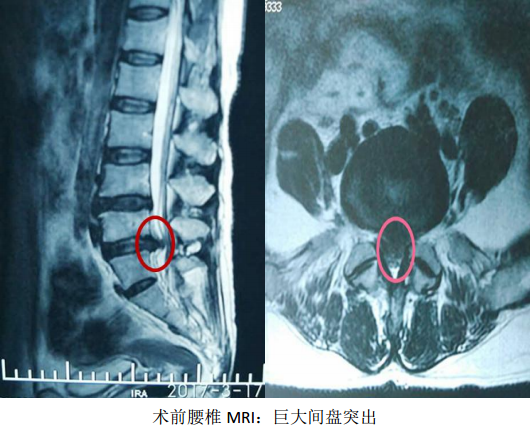

2017年3月17日,辽宁中医药大学附属医院骨伤二科,自主完成了院内首例治疗腰椎间盘突出症的椎间孔镜髓核摘除手术,开启了我院脊柱微创手术治疗的先河。此新技术的引进与开展,得到了院领导及医务处的大力支持,本次手术是由邓小磊医师在万贵良主任医师的协助下独立操作完成,受益者是一名患有腰5-骶1椎间盘突出症的57岁女性患者,此患者腰痛伴左下肢放射痛反复发作10年,复发10天,因疼痛无法下地活动行走,卧床10余天。术前经完善腰椎正侧位DR,腰椎CT和MRI等影像学检查,精准确定突出髓核的位置、性质及椎间孔骨质增生情况,详细规划手术策略,注重预判术中可能发生问题,提早制定解决方案。手术采取局部麻醉,切口约7mm,在DSA引导下,经椎间孔建立直径7mm的工作通道,使用椎间孔镜靶向摘除突岀的椎间盘髓核。手术医师在术中随时与患者语言交流,安全,顺畅。此例手术过程顺利,术后患者疼痛即刻缓解,并可下地行走。

脊柱内镜装置是由一个操作通道,一个光源通道和两个注水通道组成,术中操作时采用局部麻醉,经皮肤切一7mm大小的切口,在X线监视下,穿刺到突出的间盘,经过扩张通道后,椎间孔镜避开神经,进入病变部位,可视下摘除突出的间盘,达到治疗目的。脊柱内镜可根据术中需要,将图像放大30-50倍,可视下清晰靶向摘除突出的髓核,具有创口小,组织损伤少,安全性高,术后恢复快等特点,颠覆了传统的手术方式,此技术真正实现了腰椎间盘突出症的微创治疗,是快速康复理念的典型代表。